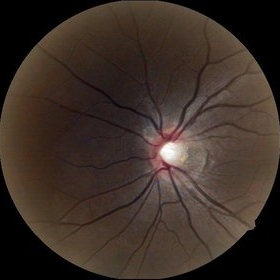

Glaucomatous Optic Atrophy

Sep 20 2014 by Mehul A Shah

A 65-year-old male presented with loss of vision and found to have glaucomatous optic atrophy.

Photographer: Drashti Netralaya,Dahod

Imaging device: Zeiss ff450

Condition/keywords: glaucomatous atrophy of optic disc